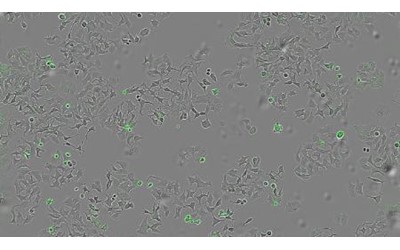

آنتونیو هورتادو، پژوهشگر دانشگاه سالامانکای اسپانیا در بیانیه‌ای گفت: «این تحقیق نشان می‌دهد که پروتئین‌های باکتریایی می‌توانند به‌عنوان ابزارهای درمانی ضدتومور مورد استفاده قرار گیرند.» تیم پژوهشی با انجام آزمایش‌هایی روی گونه‌های جهش‌یافتهٔ وبا که فاقد این پروتئین بودند همچنین روی نوع دیگری از باکتری که به‌صورت ژنتیکی طوری تغییر یافته بود که فقط HapA تولید کند، نشان داد که تنها در حضور HapA، زنده‌مانی سلول‌های توموری کاهش می‌یابد. آن‌ها همچنین بررسی کردند که آیا HapA در برابر انواع مختلف غده‌های سرطانی مؤثر است یا نه، و برای این کار مایعی حاوی تمام پروتئین‌های ترشح‌شده توسط باکتری را روی رده‌های سلولی سرطان پستان، روده و پانکراس اعمال کردند.

هورتادو گفت: «ما می‌خواستیم ببینیم آیا سلول‌های انسانی از انواع مختلف غده سرطانی، پس از تماس با این مواد باکتریایی، به‌ویژه با پروتئین HapA، باز هم زنده می‌مانند و می‌توانند تکثیر شوند یا نه.» یافته‌های این پژوهش چشم‌اندازهای امیدبخشی برای توسعهٔ درمان‌های نوین سرطان گشوده است و نشان می‌دهد که مطالعهٔ پاتوژن‌ها (عوامل بیماری‌زا) می‌تواند مکانیسم‌های مولکولی غیرمنتظره‌ای را آشکار کند که دارای پتانسیل درمانی هستند. پژوهشگران افزودند که توانایی HapA در فعال‌سازی انتخابی گیرنده‌های PAR-1 و PAR-2 از طریق نقطهٔ برشی متفاوت از آنزیم‌های انسانی، نشان می‌دهد که می‌توان سیگنال‌دهی سلولی را به‌صورت هدفمند تنظیم کرد و از عوارض جانبی آن جلوگیری نمود.